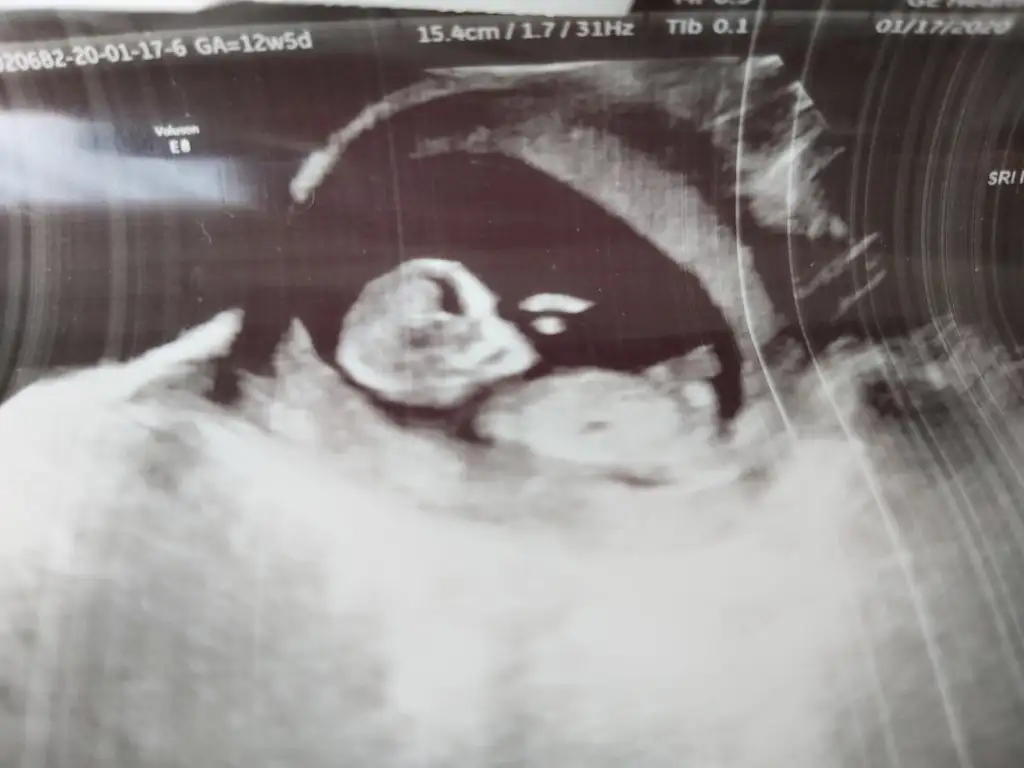

Haftam yaklaştıkça bir merak sardı.

O gözüken nub mu emin olamadım ama yine de bir atayım belki fikir yürüten olur didimm.

10+5 günlük bir kurbağa 🐸 🐣

Ne dersiniz?? Ikra meyra Ikra meyra